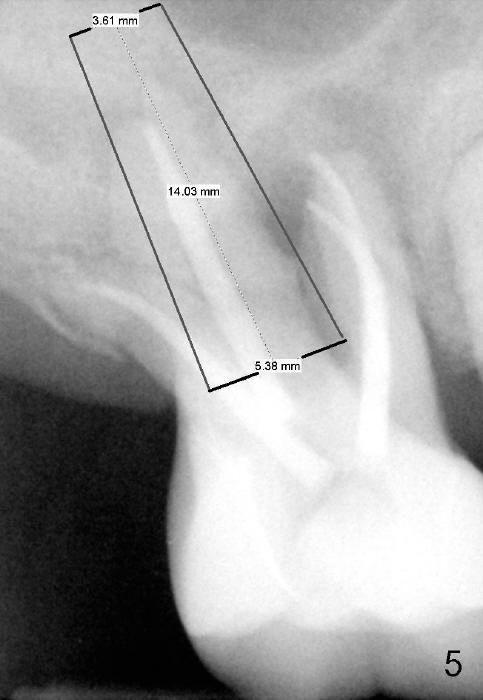

If the septum is basically intact, a 5.3x12 bone-level implant is placed in an ideal trajectory for restoration (Fig.3). The mesial and distal margin of the implant is at the level of the alveolar crests (arrows); bone graft is placed evenly to cover the coronal threads (red circles). If the septum is defective to some degree, a longer implant is placed distally (Fig.4) with more bone graft placed distally. Or the implant is placed deeper (Fig.5). If the septum is severely defective, an extra wide, but shorter implant (6.9x10 mm bone-level SM) is used (Fig.6). Or an extra wide UF implant with extra 2 mm length may offer better primary stability (Fig.6' (with sinus lift)). The primary stability of the extra wide implants is derived from contact with the mesial and distal socket walls.